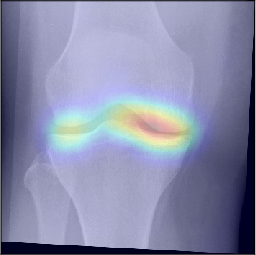

To gain insight into the basis of the CNN’s prediction, we used the GradCAM [24] approach and visualized the attention maps for the well-predicted knees. Examples of attention maps are presented in Figure 5. We observed that in various cases, the CNN paid attention to the compartment opposite to the one where degenerative change became visible during the follow-up visits. Additional examples of such attention maps are presented in Supplementary Figures 3, 4, 5 and 6.

Refer to caption

(a)

(b)

(c)

(d)

Figure 5: Examples of attention maps for progression cases and the corresponding visualization of progression derived using follow-up images from MOST datasets. Here, subplots (a) and (c) show the attention maps derived using a GradCAM approach. Subplots (b) and (d) show the joint-space areas from all the follow-up images (baseline to 84 months). Here, the subplot (b) corresponds to the attention map a) and the subplot (d) corresponds to the attention map (c).